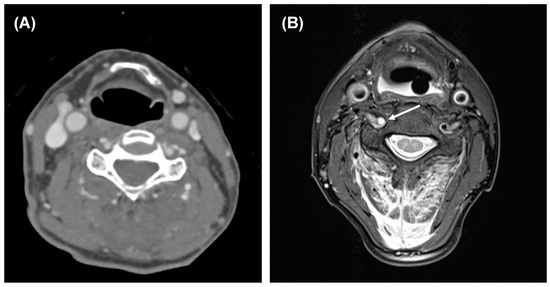

- Popp, D.; Thiedemann, C.; Baumler, W.; Ernstberger, A.; Alt, V.; Schicho, A. Modified split-scan computed tomography (CT) diagnostics of severely injured patients: First results from a level I trauma center using a dedicated head-and-neck CT-angiogram for the detection of cervical artery dissections. J. Clin. Med. 2020, 9, 2568. [Google Scholar] [CrossRef] [PubMed]

- Yamada, S.; Ohnishi, H.; Takamura, Y.; Takahashi, K.; Hayashi, M.; Kodama, Y.; Kuga, Y.; Nakase, H.; Nakagawa, I. Diagnosing intra-cranial and cervical artery dissection using MRI as the initial modality. J. Clin. Neurosci. 2016, 33, 177–181. [Google Scholar] [CrossRef] [PubMed]